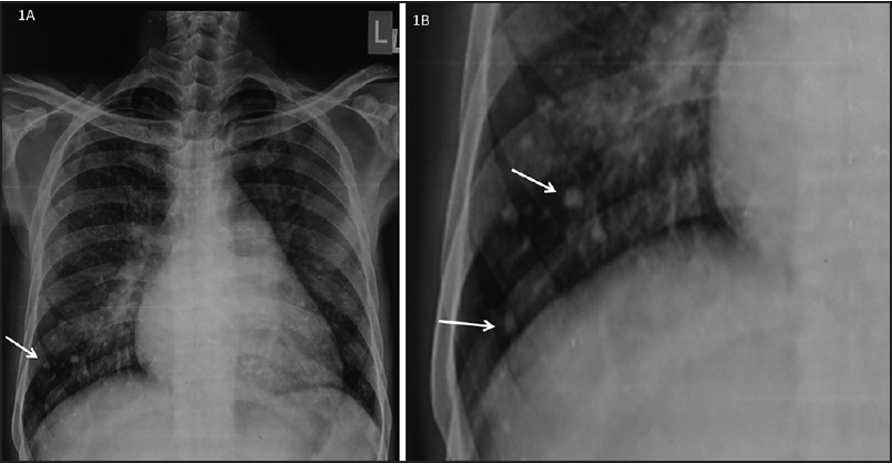

CXR Z

Left atrial enlargement

-

Mitralisation of heart: straightening of left heart border

Elevation of left mainstem bronchus

Evidence of mitral calcification

Evidence of pulmonary edema kerley’s b lines

Double contour of the right border of heart

Complication of mitral stenosis

Imaging

PA view: ⇒ Left atrial enlargement:

- Convexity or straightening of the left atrial appendage.

- Left heart border is straight or convex

- Double density of RTÂ cardiac border

- Elevation of the left main bronchus and splaying of the carina

LA view: posterior protrusion of the upper part of posterior heart border.